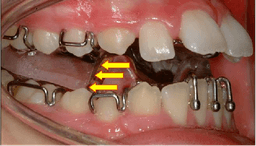

Myofunctional Treatment

Therapy focused on correcting improper muscle function in the face and mouth. Addresses oral habits, tongue posture, and swallowing patterns that can affect dental development and facial growth.